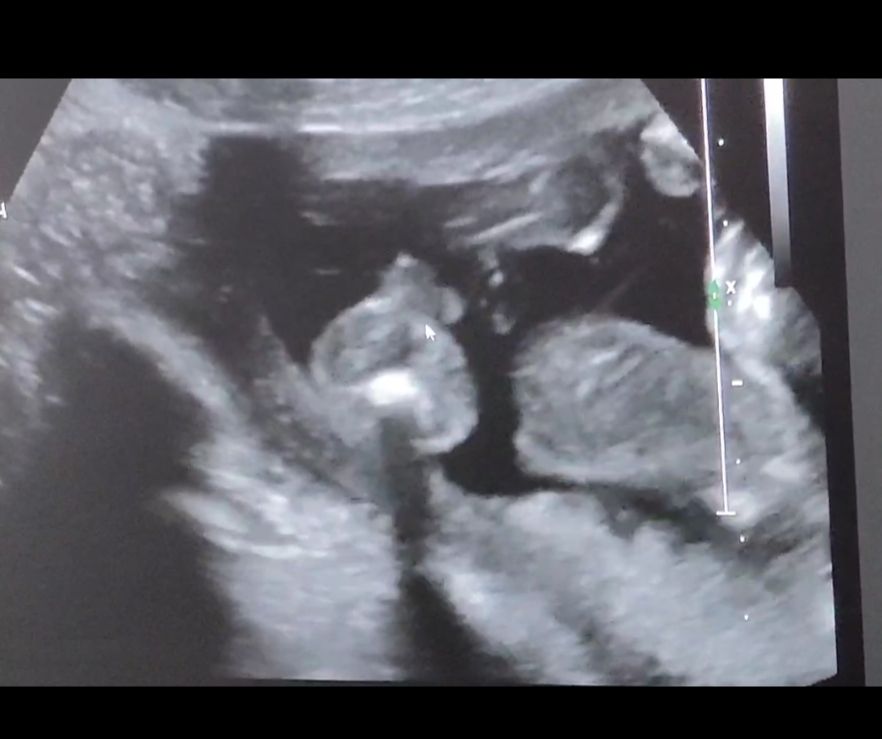

Пришли к УЗИсту узнать пол до скрининга, который сказал, что у меня замершая на 90 проц🤣УЗИст может узнал меня, сказал бесплатно скажет. А мы теперь ему до конца не доверяем. Мышкой показывает мошонку, а мы не совсем понимаем, так как смотрели минуту🤣 как будто справа ноги согнутые и булки понятно

Я, когда видео идёт, видно, что смотрим снизу на булки, ноги согнутые, а что за большой круг не понимаем

Похоже на мальчика, да. За точность не отвечаю 🤭 Там же внизу попа, указатель мышки на мошонке?

А там мошонка и ещё что-то 🤭